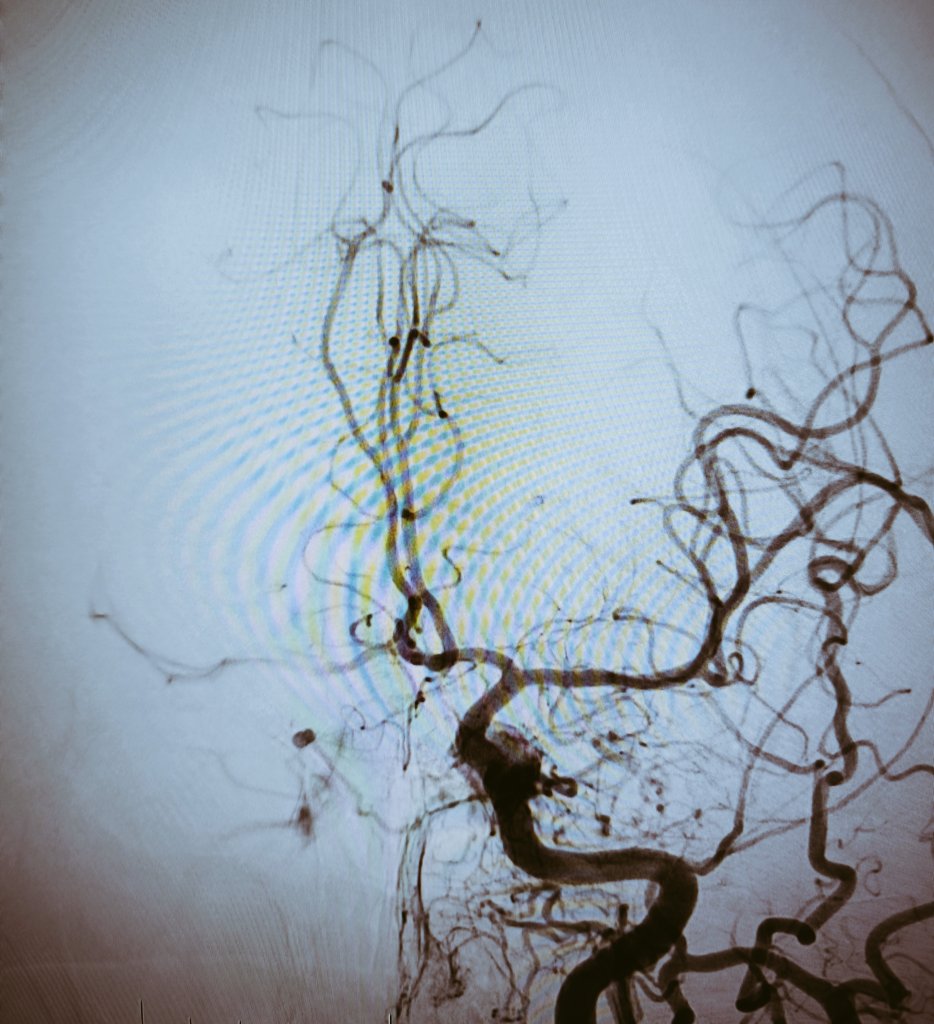

Distal occlusion in right PCA recanalized using 3Max (@PenumbraEMEA). In my opinion aspiration should be the first option in distal occlusions (let's wait for randomized trials stent versus aspiration in DMVOs).